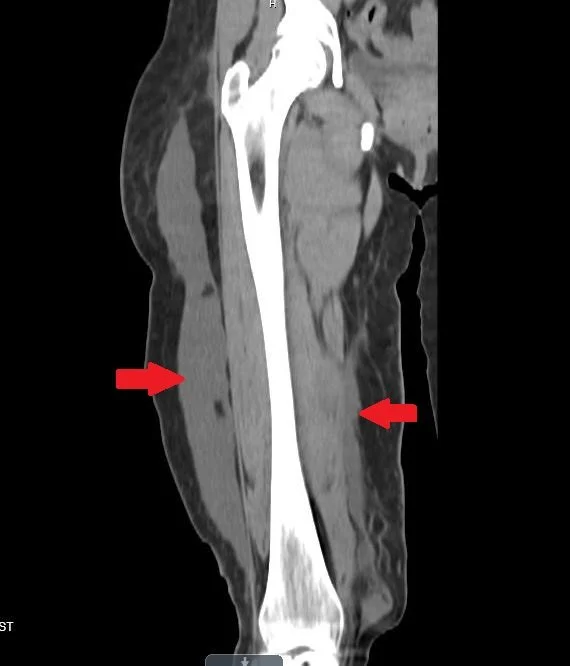

A 40 woman was run over by her own truck 5/2 and returns 5/23 with swelling of the thighTh

She had sustained a sacral and pelvic fx initially but no fx of the femur

hint: there is no femur fracture

the arrows point to the pathology

Our patient  had an internal degloving injury with fluid collecting superficial to the iliotibial band laterally and medially along the superificial fascia of the medial thigh. This is known as a Morel-Lavallee lesion. It  was named  for a French surgeon Maurice Morel-Lavallee  in 1863.

The lesion is caused by  disruption of capillaries resulting in an effusion containing hemolynph and necrotic fat.  There is a chronic inflammatory reaction which can lead to the formation of a capsulated lesion which can continue to grow with time.   Missing this lesion can result in skin necrosis, pain and infection.

MRI is the modality of choice in discovering this lesion but as in our patient a fluid wave can be seen on physical exam and the collection is often visible on CT.